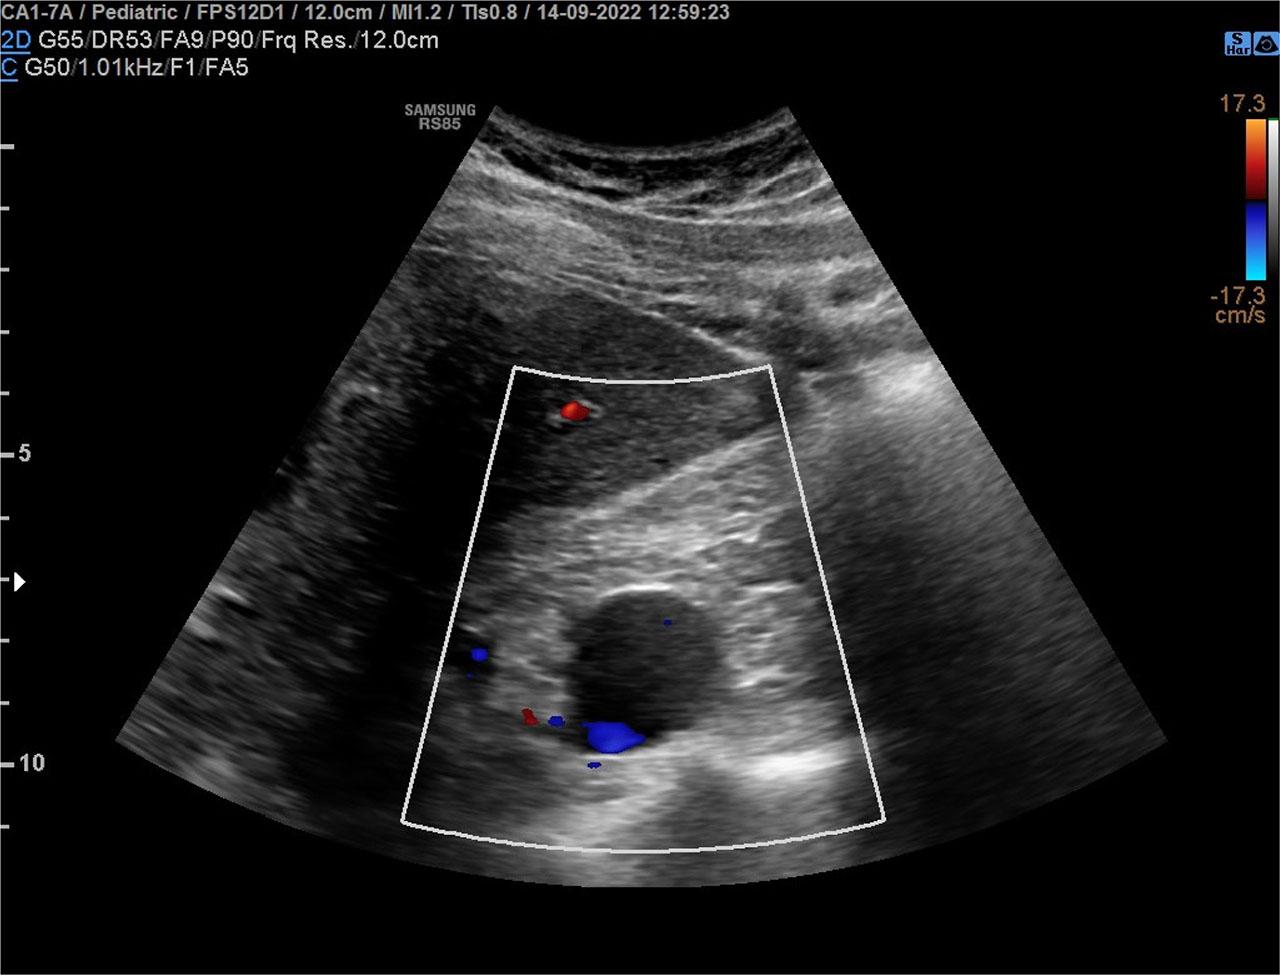

Figure 1.